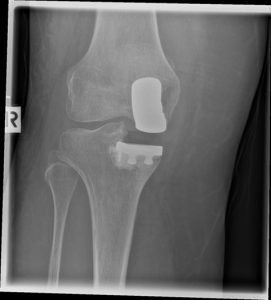

(Bild links: Röntgenbild eines Teilgelenkersatzes mit zu großer Prothesenkomponente. Dadurch resultierte ein X-Bein mit Überlastung des erhaltenen Gelenks und ein Instabilitätsgefühl beim Gehen.)